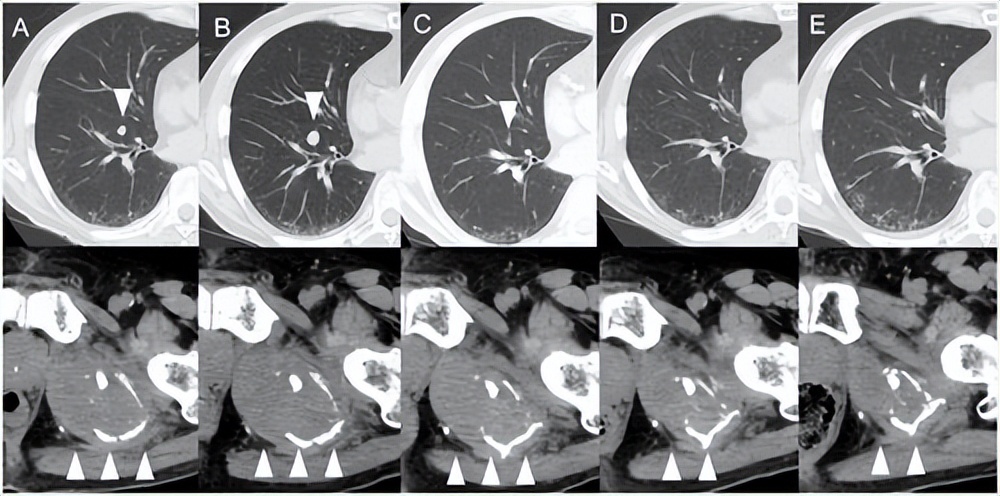

这是一位肝癌出现肺转移患者在接受阿替利珠单抗联合贝伐珠单抗治疗后的肺部转移瘤的CT断层扫描图,其中图A到E箭头所指示的就是用药第1-5个疗程肺部转移瘤的大小。

可以发现,在第二个疗程,也就是图B,明显发现转移瘤体积增加,而到了第3、4、5疗程,转移瘤体积又出现了明显缩小,最后完全消失[1]。